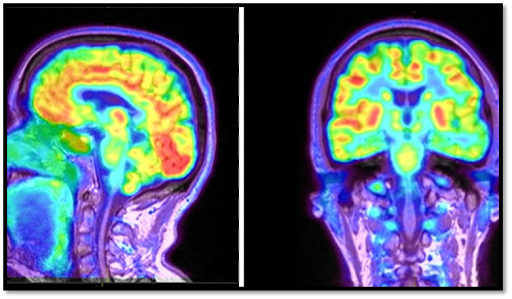

Figure - 3: PET Scan of a Human Brain [6]

2.2 Positron emission tomography (PET)

PET (Positron Emission Tomography) has gained popularity as an essential imaging technique for radiotherapy treatment planning. Its applications extend beyond traditional diagnostic purposes, as it serves as a valuable therapy response technique. PET's incorporation in radiotherapy has led to improved staging and target delineation, enhancing treatment precision and patient outcomes. The introduction of integrated PET/CT systems has played a crucial role in the widespread adoption of PET in treatment planning. Combining PET with CT (Computed Tomography) scans provides comprehensive anatomical and functional information, allowing for accurate localization of tumors and their response to treatment. This integration has revolutionized treatment planning by offering a more holistic view of the patient's condition.

As a result, many radiation therapy departments now have access to PET imaging or have their own dedicated PET scanners. The technology has become an integral part of modern radiotherapy practices, helping clinicians tailor treatment approaches based on real-time tumor response data. This has significantly improved treatment efficacy while minimizing radiation exposure to healthy tissues. However, like any advanced technology, PET imaging in radiotherapy is continuously evolving, and challenges are being addressed to ensure seamless integration into treatment planning. Ongoing research and development focus on refining PET image quality, enhancing data analysis methods, and optimizing workflow to further optimize radiotherapy outcomes. Overall, PET's prominence in radiotherapy treatment planning has revolutionized cancer care, enabling personalized and precise treatment strategies that maximize therapeutic benefits and improve patients' quality of life. [3]